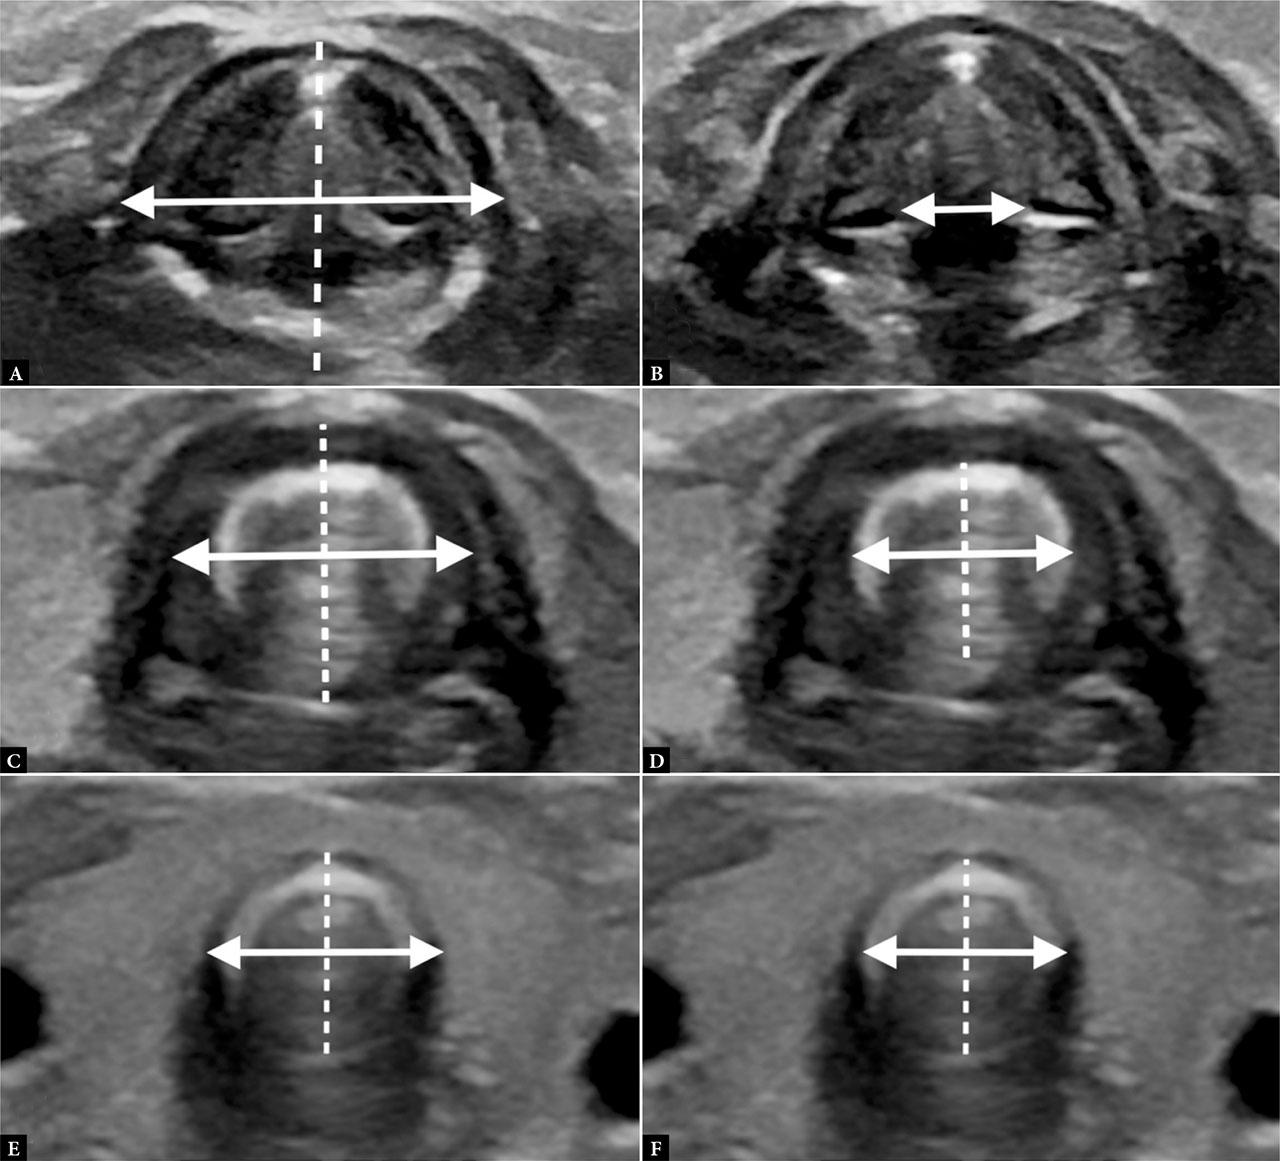

To maximize participant comfort, minimize procedure duration, and enhance measurement reproducibility, all ultrasound assessments adhered to a predetermined protocol. Recordings were stored in DICOM format. After data collection, measurements of individual structures of the larynx and trachea were performed using computer software (Horos, Nimble Co LLC d/b/a Purview). Figure 1 illustrates the ultrasound images of the discussed structures, along with detailed measurement techniques. Statistical analyses were performed using SAS/STAT software.

Measurements of: A. laryngeal width (double-arrow line) – transversely from the outer borders of the thyroid cartilage at the level of the glottis; laryngeal depth (dashed line) – sagitally between the outer borders of the thyroid and annular cartilages; B. glottis width (double-arrow line) – between the medial borders of the arytenoid cartilages; C. subglottic width (double-arrow line) – transversely from the outer borders of the annular cartilage; subglottic depth (dashed line) – sagitally from the outer borders of the annular cartilage; the measurements are taken at the level of the arch of the annular cartilage. D. subglottic lumen width (double-arrow line) – transversely from the inner borders of the annular cartilage; subglottic lumen depth (dashed line) – sagitally medially from the inner borders of the annular cartilage; E. tracheal width (double-arrow line) – transversely from the outer borders of the tracheal cartilage; tracheal depth (dashed line) – sagitally from the outer border of the tracheal cartilage to the tracheal muscle membrane; F. tracheal lumen width (double-arrow line) – transversely from the inner borders of the tracheal cartilage; tracheal lumen depth (dashed line) – sagitally from the inner border of the tracheal cartilage to the tracheal muscle membrane